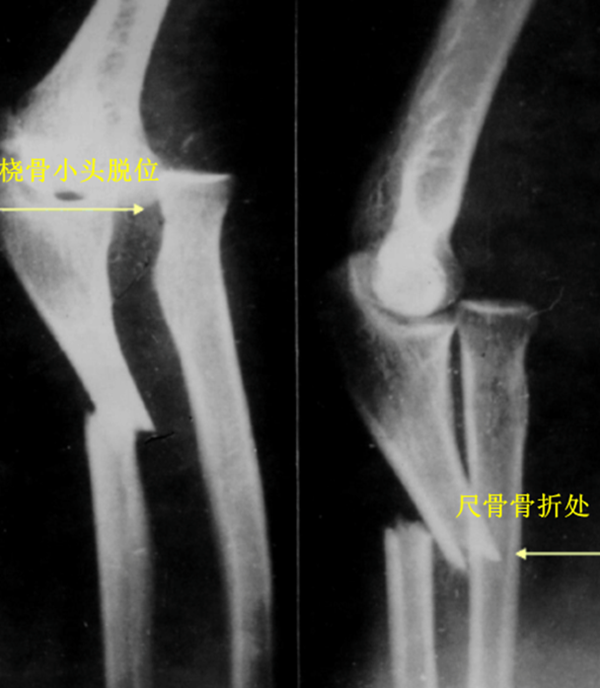

新鲜孟氏骨折的X线片评估内容必须包括标准尺桡骨正侧位片,摄片范围包括腕关节和肘关节。正常情况下,无论肘关节屈伸角度如何,经过桡骨颈和桡骨头中心的线应该通过肱骨小头的中心。

目前临床上主要采用Bado分型方法,即根据尺骨骨折和桡骨小头脱位的方向,分为Ⅰ、Ⅱ、Ⅲ、Ⅳ四型。

Ⅳ型(特殊型):桡骨上1/3骨折,桡骨头向前方脱位,合并的尺骨与桡骨骨折水平面相同,约占5%。